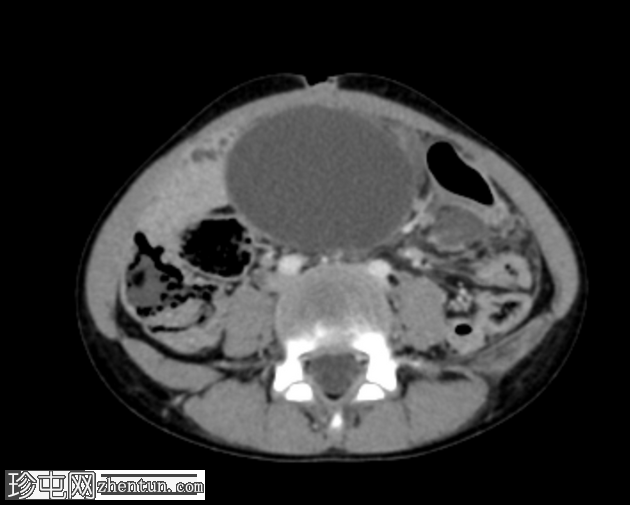

轴位增强扫描(门静脉期)

阑尾过长,跨越中线向左侧延伸。阑尾呈扩张状态,充满液体(8mm),管壁增厚并强化,近端可见多发性穿孔。阑尾周围脂肪间隙模糊,可见液体密度影和管腔外气体。未见脓肿。